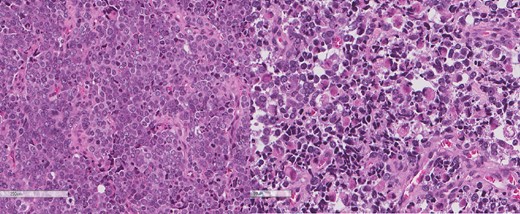

A review of the previously resected esophageal tumor revealed the presence of both epithelial and sarcomatous components. The epithelial component was composed of moderately to poorly differentiated adenocarcinoma, while the sarcomatous component showed hyperchromatic round to spindle cells with scant cytoplasm and frequent mitoses (Figs 3–6). The intrathoracic tumor showed a similar morphology as the sarcomatous component of the esophageal tumor, with focal rhabdomyoblastic differentiation (Fig. 7). The latter was strongly positive for desmin, myogenin, and MyoD1 and was focally positive for synoplastin, CD56, CD 10, and FL1.

The intrathoracic tumor shows similar morphology to the sarcomatous component of the esophageal tumor, with focal rhabdomyoblastic differentiation.